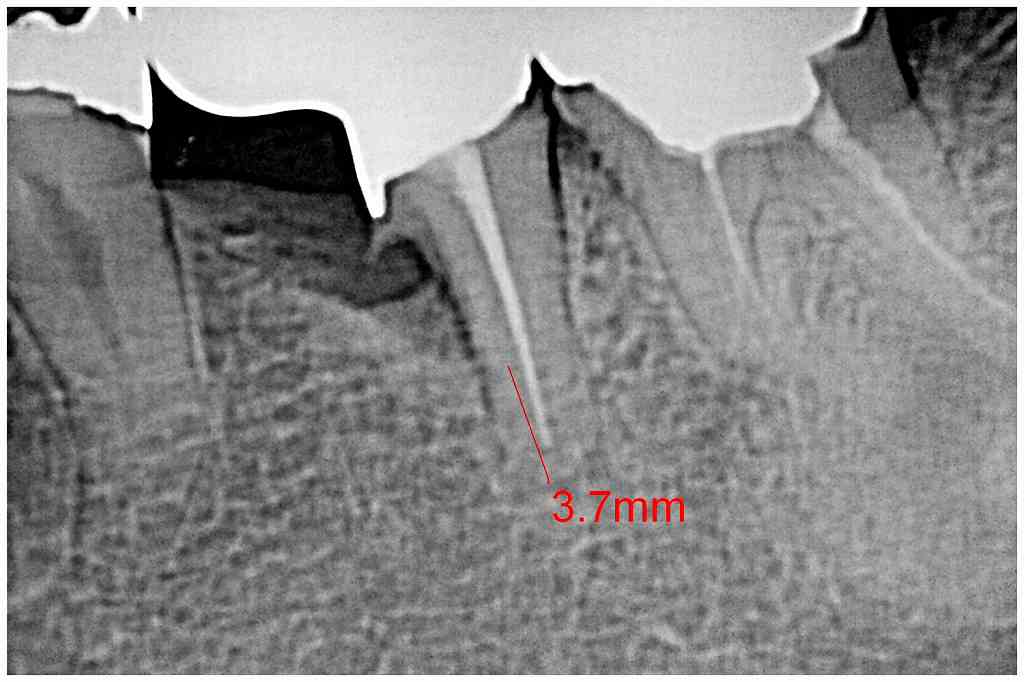

左下の奥歯のインプラント埋入|お知らせ |広島市安佐南区の歯科医院 左下の奥歯のインプラント埋入 トップ お知らせ・ブログ お知らせ 左下の奥歯のインプラント埋入 左下の奥歯のインプラント埋入 左下の6番ヘミセクション このクラウンが揺れてきました 骨吸収が認められます 割れているため抜歯となりました 抜歯しました 埋入していきました 補填材を入れ縫合して終了です このように埋入しています Web診療予約 初めての方へ 選ばれ続ける理由 院内設備について 歯が痛いしみる一般歯科 歯がぐらぐらする歯周病 健康な歯を保ちたい予防歯科 子供の虫歯予防をしたい小児歯科 銀歯をセラミックに審美歯科 白い歯を目指しませんか?ホワイトニング 矯正専門医がいるので安心矯正歯科 抜けた歯を補いたいインプラント・入れ歯 医院案内 スタッフ紹介 メリィハウス歯科クリニックオフィシャルホームページ ラベンダー歯科クリニックオフィシャルホームページ お知らせ・ブログ ホーム 診療科目 一般歯科 歯周病治療 予防治療 小児歯科 審美治療 ホワイトニング 矯正歯科 入れ歯・インプラント マウスピース矯正 初めての方へ 院長・スタッフ 設備紹介 医院案内・アクセス メニューを閉じる